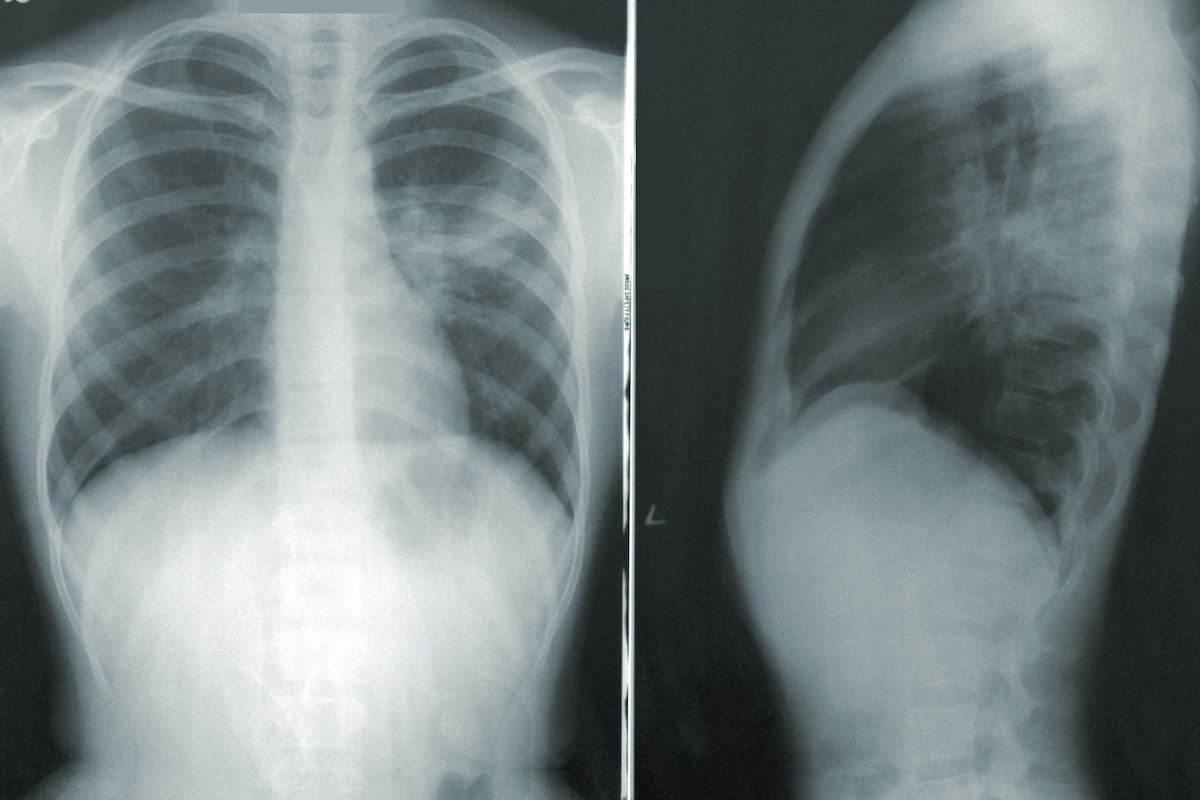

Η νοσοκομειακή πνευμονία είναι μια λοίμωξη των πνευμόνων που εμφανίζεται τουλάχιστον 48 ώρες μετά την εισαγωγή στο νοσοκομείο. Συνήθως είναι πιο σοβαρή από άλλες λοιμώξεις του αναπνευστικού, καθώς το ανοσοποιητικό σύστημα των ασθενών είναι συχνά εξασθενημένο, ενώ τα παθογόνα που κυκλοφορούν στο νοσοκομειακό περιβάλλον είναι πιο ανθεκτικά και πιο επιθετικά σε σχέση με εκείνα της κοινότητας.

Η μορφή πνευμονίας που εξετάστηκε στη μελέτη, η μη σχετιζόμενη με μηχανικό αερισμό νοσοκομειακή πνευμονία (NV-HAP), αφορά ασθενείς που δεν βρίσκονται σε μηχανικό αερισμό.

Η νοσοκομειακή πνευμονία σε ασθενείς που δεν βρίσκονται σε μηχανικό αερισμό προκύπτει συχνά όταν υγρά από το στόμα ή τον φάρυγγα περνούν στους πνεύμονες. Τα παθογόνα του αναπνευστικού που σχετίζονται με το νοσοκομείο εντοπίζονται πιο συχνά σε ασθενείς που δεν μπορούν να απομακρύνουν τις στοματικές εκκρίσεις, σύμφωνα με τον Brett Mitchell, εκ των συγγραφέων της μελέτης στο Avondale University στην Αυστραλία.